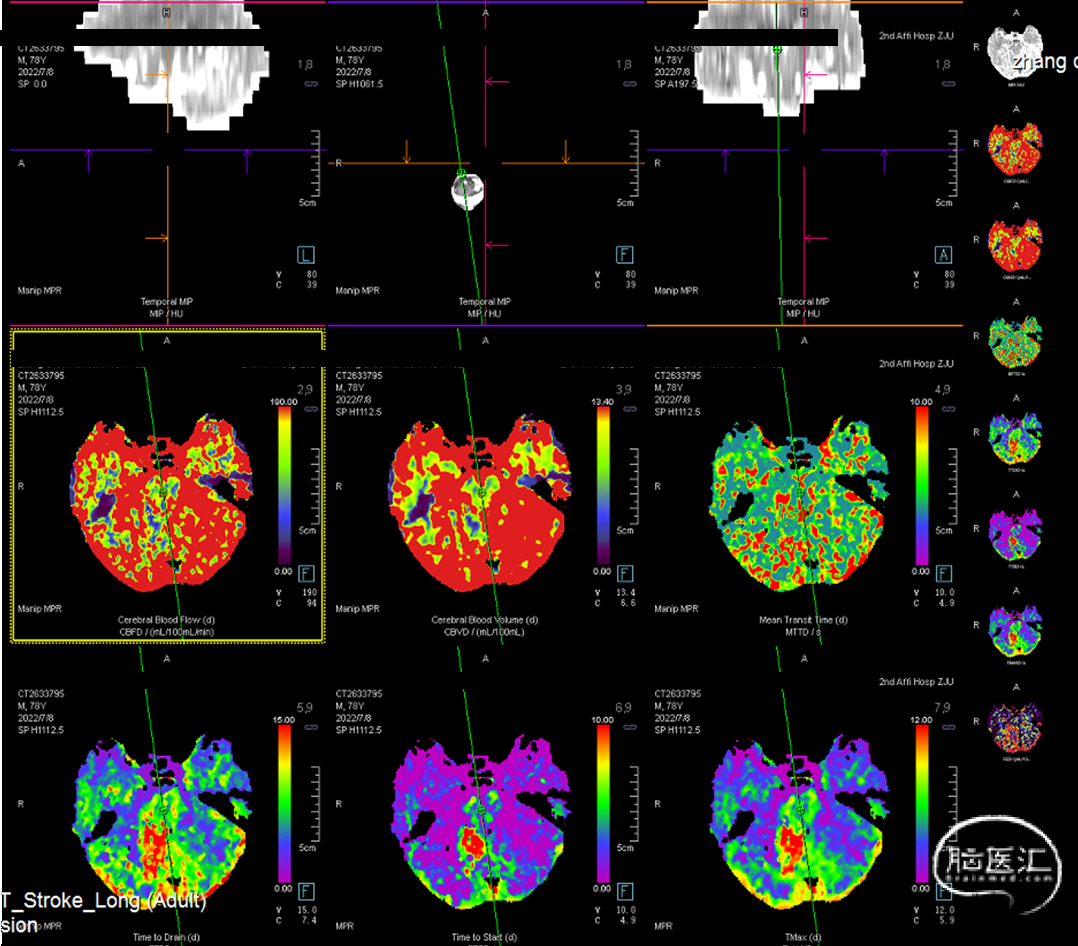

综合术前辅助检查,(Core+pen)/Core=3.58;Pen>15ml;Core<70ml(图3);发病时间小于24小时,存在取栓指征,但是当地医院手术经验告诉我们左侧椎动脉慢性闭塞,且开通异常困难,常规手术方案很难成行,术前制定合理且可行的手术方案至关重要。方案1:仍采用左侧椎动脉+基底动脉取栓的正向开通方案,可能会继续浪费大量时间,甚至最后以失败告终。方案2:采用右侧椎动脉入路,由于右侧椎动脉V4段发育不良,当地医院已尝试过超选,证实无法通过V4段至基底动脉建立取栓通路。方案3:既往有文献报道开颅椎动脉直视下穿刺取栓,虽然方案可行,但我院无类似手术经验,贸然尝试风险难以把控。方案4:回顾当地医院取栓影像资料,发现双侧颈内动脉后交通呈胚胎型,是否可能通过后交通跨循环逆向超选至基底动脉取栓。患者平卧DSA床,全麻插管成功后,用碘伏常规消毒手术区皮肤,铺无菌巾单。取双侧股动脉为穿刺点,于14时00分seldinger法穿刺成功后分别置入8F穿刺鞘和5F 短鞘。行全脑血管造影显示左侧椎动脉起始部闭塞,颈升动脉通过肌支代偿V2及以远的椎动脉血流,右侧椎动脉V4段发育不良,单纯供应右侧PICA,双侧后交通动脉胚胎型。(图9,图10)首先我们仍尝试传统入路进行超选左侧椎动脉,发现左侧椎动脉开口闭塞,斑块质地坚硬,微导丝微导管无法通过。短暂尝试无果后,迅速改为右侧椎动脉入路,发现将微导丝塑型成“J”型或成袢,均无法到达右侧椎动脉V4段,遂果断决定采用跨循环取栓方案。将5F VERT造影导管超选至左侧锁骨下动脉,进行正向血流监测。6F 90cm长鞘(cook)及5F 125cm Navien导管在泥鳅导丝带领下超选进入右侧颈内动脉岩骨段。随后将Rebar18微导管在Synchro2微导丝带领下超选至大脑中动脉,并将Navien带领至右侧颈内动脉交通段。微导丝微导管回撤至颈内动脉,路图下Synchro2微导丝带领Rebar18逐步通过右侧后交通动脉,再在透视下经右侧大脑后动脉P1段盲超选至基底动脉下段。(图11-13)手推造影确认Rebar18微导管已突破血栓段,并在基底动脉真腔内。(图14)经Rebar18释放一枚solitaire FR支架(4mm×20mm)覆盖血栓段。SWIM技术负压下抽拉支架1次,抽拉过程中时刻注意系统张力,逐步回撤支架同时适度回撤Navien释放张力,以保证Navien贴近后交通开口而不向后交通动脉内继续深入。撤出支架后,Navien原位保持负压约30秒。(图15)造影复查见基底动脉及其分支再通,支架取出少量血栓(图18)。于14时45分达到远端血流mTICI3级,10分钟后复查造影显示血管通畅,于14时55分末次造影见远端血流维持mTICI3级。(图16,17)术中Dynamic CT未见明显术区出血(图19)。遂缝合穿刺点,结束手术。手术顺利,术中病人情况稳定。术末血压115/58mmHg,脉搏70次/分,呼吸12次/分,氧饱和度100%。术毕送重症监护室。图9. 双侧椎动脉造影:左侧椎动脉起始部闭塞,左侧颈升动脉肌支和右侧椎动脉通过脊髓支代偿V2及以远的椎动脉血流;右侧椎动脉V4段发育不良,单纯供应右侧PICA